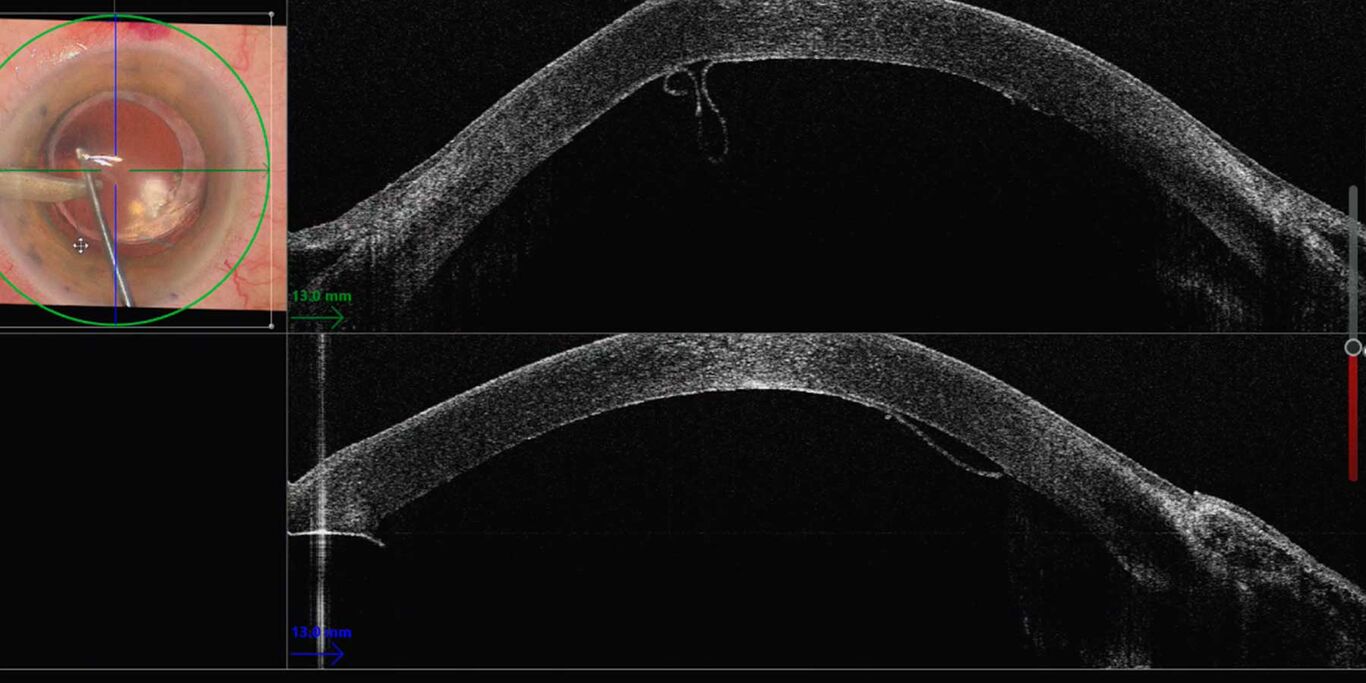

Ophthalmology Visualization in Complex Cataract Surgery Science Lab Leica Enfocus I need assistance/training in how to. I need repair, technical service, spare parts or service contract. The optimized enfocus design lets you work in a more comfortable and relaxed posture at the microscope. View and download leica microsystems enfocus oct user manual online. The enfocus intraoperative oct system built into the proveo 8 microscope, can help surgeons overcome these uncertainties. Leica Enfocus.